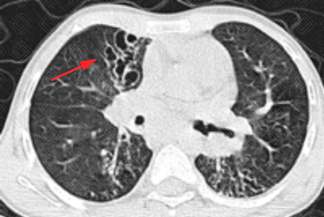

Texto alternativo para a imagem Créditos: Dra. Elazir Mota - Rio de Janeiro/RJ.

Descrição das imagens: Paciente infantil do sexo masculino, 11 anos, exame de acompanhamento de fibrose cística. Na tomografia computadorizada do tórax, observam-se extensas bronquiectasias varicosas bilaterais, mais evidentes à direita (setas vermelhas).

• Tomografia computadorizada do tórax: A fibrose cística cursa principalmente com espessamento das paredes brônquicas e bronquiectasias. As bronquiectasias podem ser varicosas, cilíndricas ou císticas; geralmente são bilaterais e predominam nos lobos superiores. A impactação mucoide, o preenchimento das pequenas vias aéreas e as consolidações também são achados frequentemente encontrados.